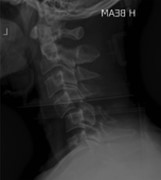

A game of two discs: a case of non-contiguous and occult cervical spine injury in a rugby player

Michael D. O'Sullivan and others

Journal of Surgical Case Reports, Volume 2016, Issue 3, March 2016, rjw031, https://doi.org/10.1093/jscr/rjw031